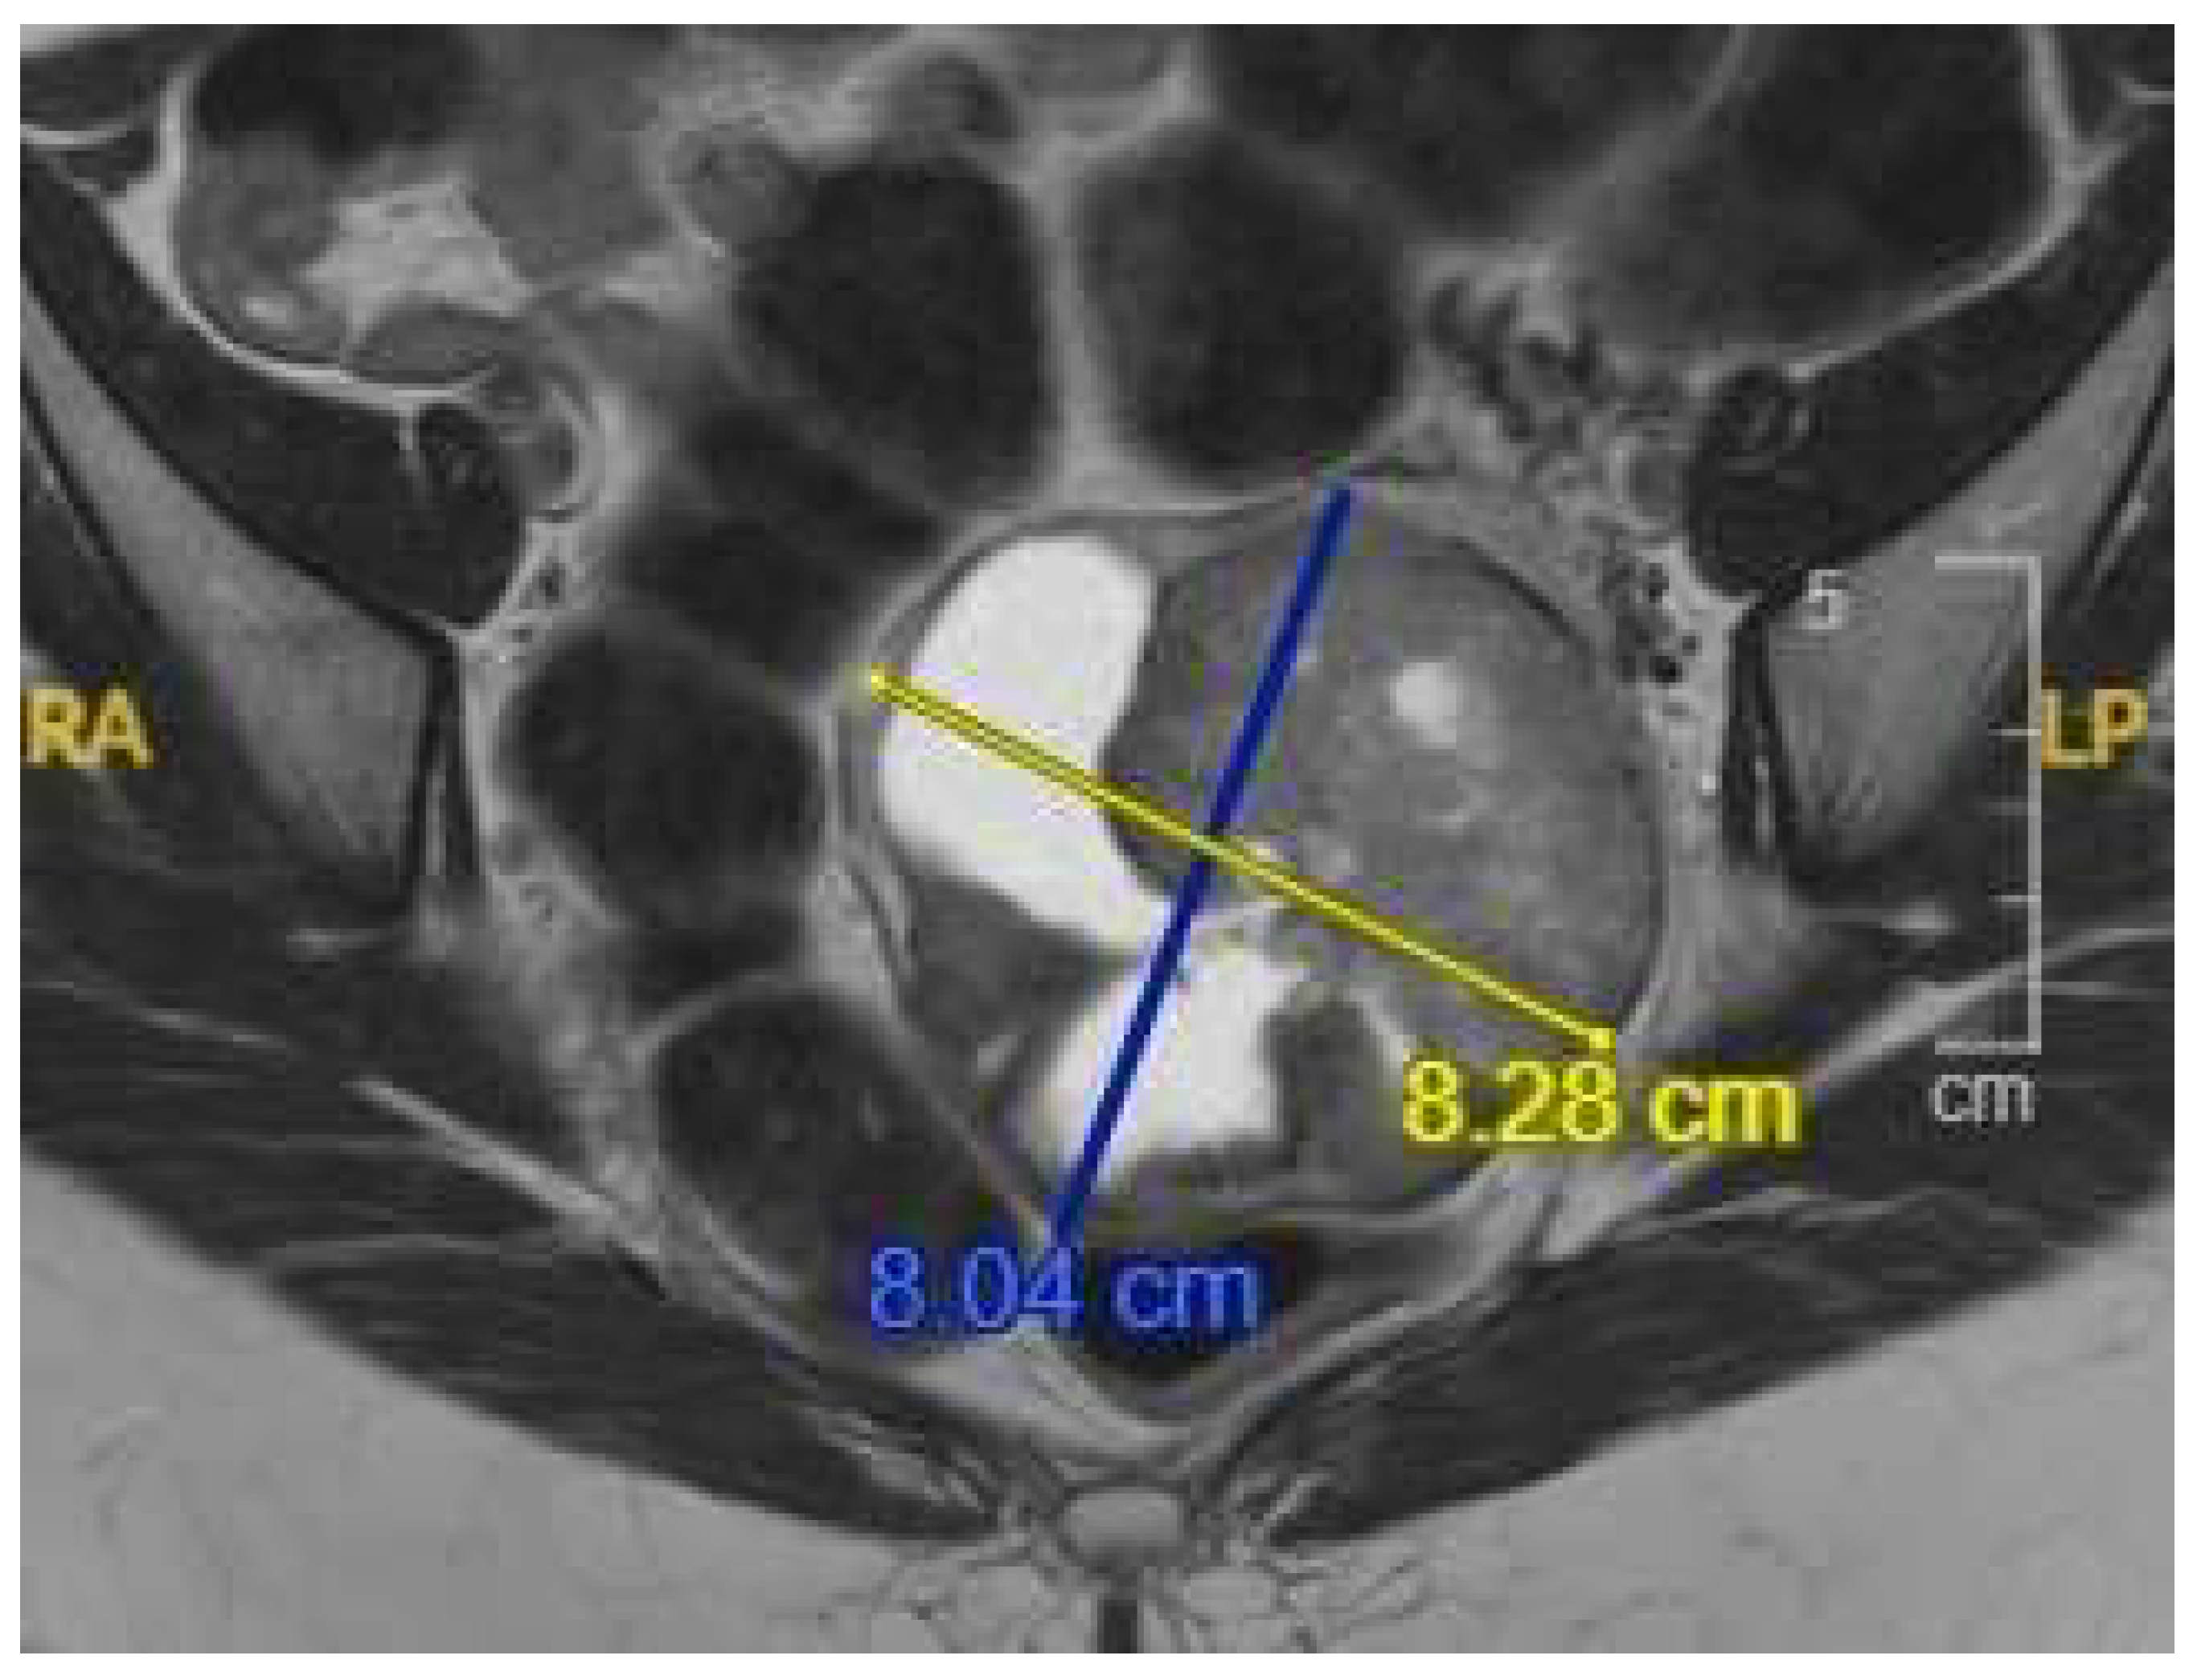

2. Case Presentation